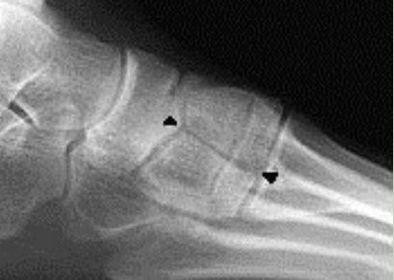

What is this? What is shown by A and B? | STJ coalition A = talar neck spurring B = Halo or 'C' sign |

What is this? | Posterior talocalcaneal coalition |

What is shown by A and B? | A = Talonavicular coalition B = Calcaneocuboid coalition |

What is this? | Cuboid-navicular coalition |